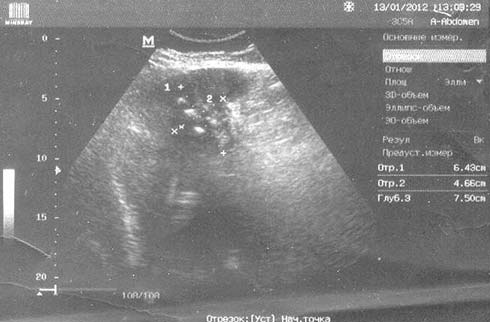

При повторной консультации хирурга (29.01), учитывая отсутствие положительной динамики при УЗИ, повышенный уровень СРБ, СОЭ в анализах для исключения опухоли желчного пузыря назначена компьютерная томография (КТ) органов брюшной полости и забрюшинного пространства. При КТ органов брюшной полости и забрюшинного пространства с контрастным усилением (30.01) в проекции желчного пузыря определяется инфильтрация печеночной паренхимы с вовлечением пузыря, стенки которого неравномерно утолщены, накапливают контрастное вещество, в просвете пузыря множественные конкременты со взвесью. Внутрипеченочные и общий желчный проток не расширены. В области ворот печени и перипузырном пространстве скудное количество жидкости. Забрюшинные лимфоузлы не увеличены. Остальные органы брюшной полости и забрюшинного пространства без особенностей. Заключение: КТ-картина требует дифференциальной диагностики между острым деструктивным холециститом и неопроцессом желчного пузыря (рис. 2).

Рис. 2. КТ-брюшной полости с контрастированием. Инфильтрат в области желчного пузыря.